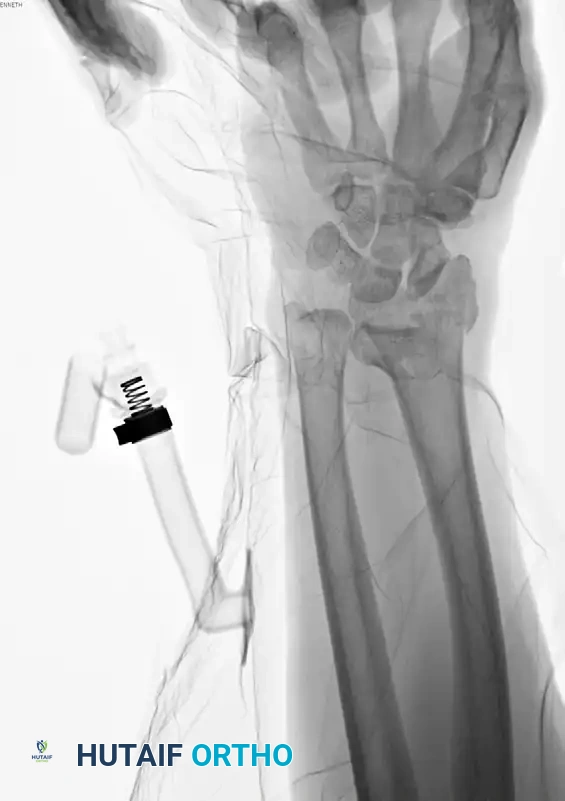

Image

Preoperative AP radiograph demonstrating a highly comminuted, unstable distal radius fracture.

Preoperative Lateral radiograph highlighting severe dorsal comminution and loss of volar tilt.